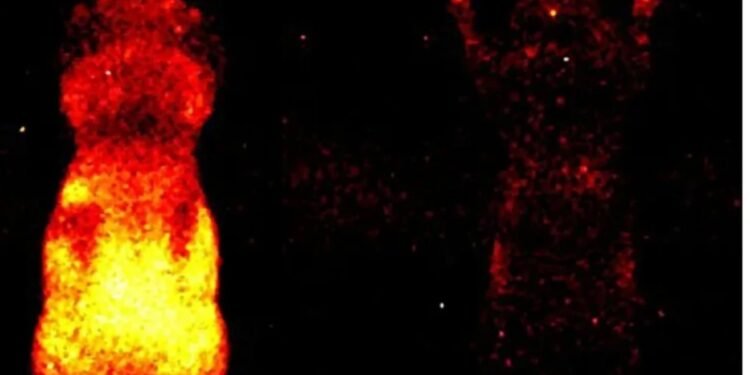

Əvvəlki tədqiqatlarda foton emissiyası yalnız ayrı-ayrı hüceyrələr səviyyəsində müşahidə olunmuşdu. Lakin Kalqari Universitetindən dosent Daniel Oblakın rəhbərlik etdiyi qrup bütün orqanizm səviyyəsində – həm canlı, həm də ölü vəziyyətdə – bu parıltını qeydə almağa nail olub.

Tədqiqat üçün siçanlar xüsusi qaranlıq kameraya yerləşdirilib və iki saatlıq eksperiment zamanı canlı heyvanların bədəni boyunca yayılan zəif işıq, baş, daxili orqanlar və pəncələrdə “isti nöqtələr” şəklində qeydə alınıb. Alimlər hesab edirlər ki, gələcəkdə bu zəif parıltının monitorinqi travmaların və müxtəlif xəstəliklərin erkən diaqnostikası üçün istifadə oluna bilər.